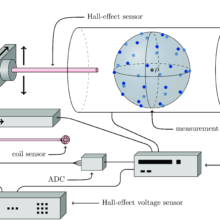

Magnetic fields and imaging technologies

- 17 June 2025,

- Magnetic fields are at the core of many imaging technologies. A widely known modality is MRI, a standard procedure in medical imaging, which is however limited...